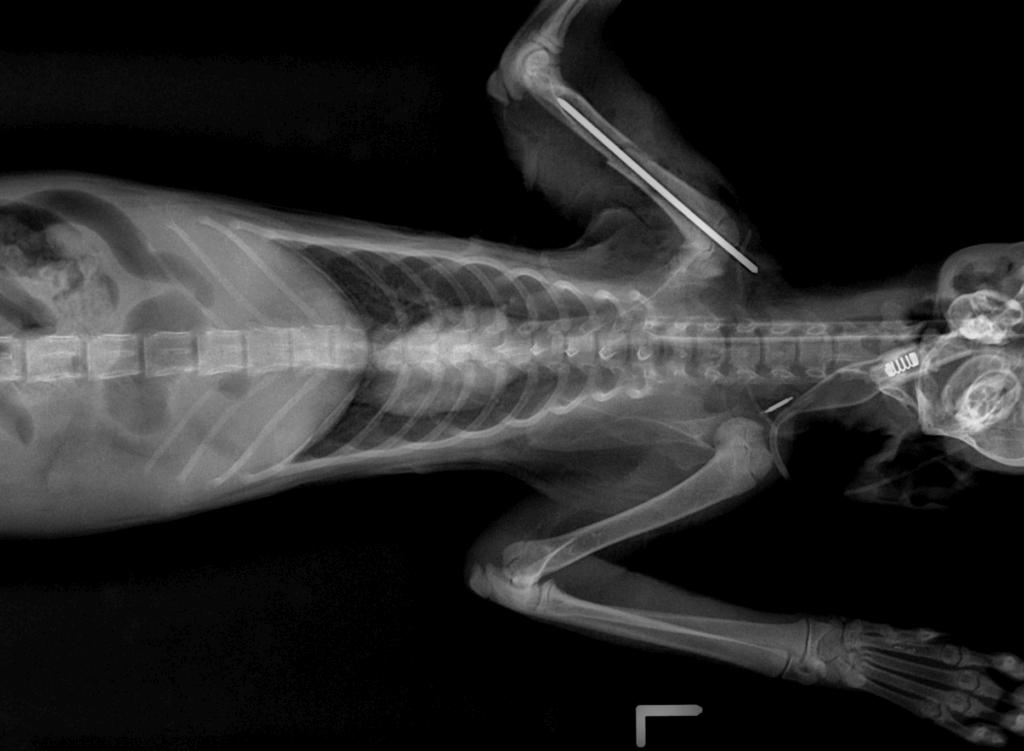

貓咪經醫療中心李獸醫師檢查後,發現上顎有傷口、右前肢蜷縮無法撐地,X 光檢查下發現右前肢肱骨交錯性骨折,肺部支氣管炎症反應嚴重,推測是天氣驟變肺部感染、貓活動力變差不慎由高處摔落或車禍所造成。

動保處獸醫師李建沛表示,根據毛寶貝醫療中心傷病動物案例顯示,貓咪常因為高處不慎摔落、車禍而造成不同程度的傷害,尤其以顏面受創及肢體骨折居多,若胸腔受創嚴重造成橫膈破裂,則須緊急進行手術治療才能避免猝死。這隻虎斑白貓研判可能是連日天雨視線不佳遭車輛擦撞,造成前肢肱骨骨折及臉部上顎受創,所幸臉部傷勢不嚴重,骨折部位經過手術治療後已回復行走及跳躍功能。